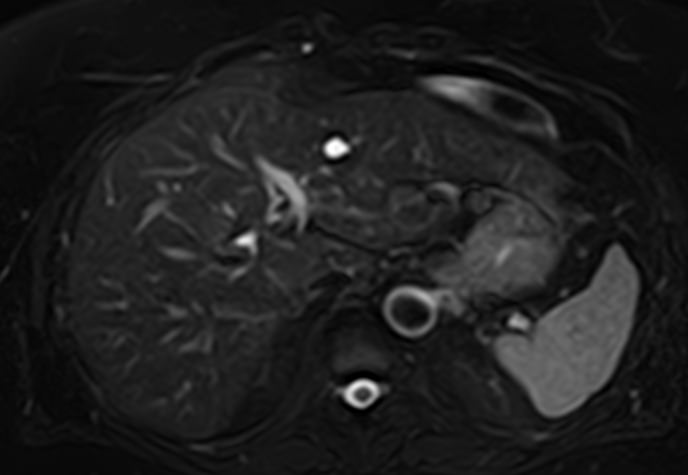

В клинике «Доступная медицина» МР томография проводится на новейшем высокопольном томографе экспертного класса TOSHIBA VANTAGE TITAN 1,5 Тесла. Высокая индукция магнитного поля обеспечивает повышенную четкость изображений при проведении обзорной МРТ брюшной полости, что гарантирует точность и эффективность диагностики заболеваний печени, желчного пузыря, поджелудочной железы и селезенки. Аппарат послойно сканирует исследуемую область с шагом от 1 мм в различных плоскостях, затем трансформирует результаты в трехмерные изображения превосходного качества. Для уточнения характера патологических изменений одного из органов назначается прицельная МР томография данного органа.

Для расширения возможностей диагностики, при необходимости уточнения характера патологических изменений применяется контрастное усиление. Для этого в вену вводится контрастный препарат, содержащий металл гадолиний (Магневист, Гадовист и др). Препарат фиксируется в очагах поражения, позволяя диагностировать их при минимальных размерах, что бывает особенно важно в диагностике опухолей.

- Доброкачественные образования (кисты, гемангиомы) и злокачественные опухоли органов брюшной полости (первичные опухолевые очаги и метастатические поражения, в том числе, брюшины).

- Заболевания печени (жировая инфильтрация печени, гепатиты, цирроз и др).

- Заболевания желчного пузыря и желчевыводящих протоков, поджелудочной железы (желчекаменная болезнь, холецистит, панкреатит и др).